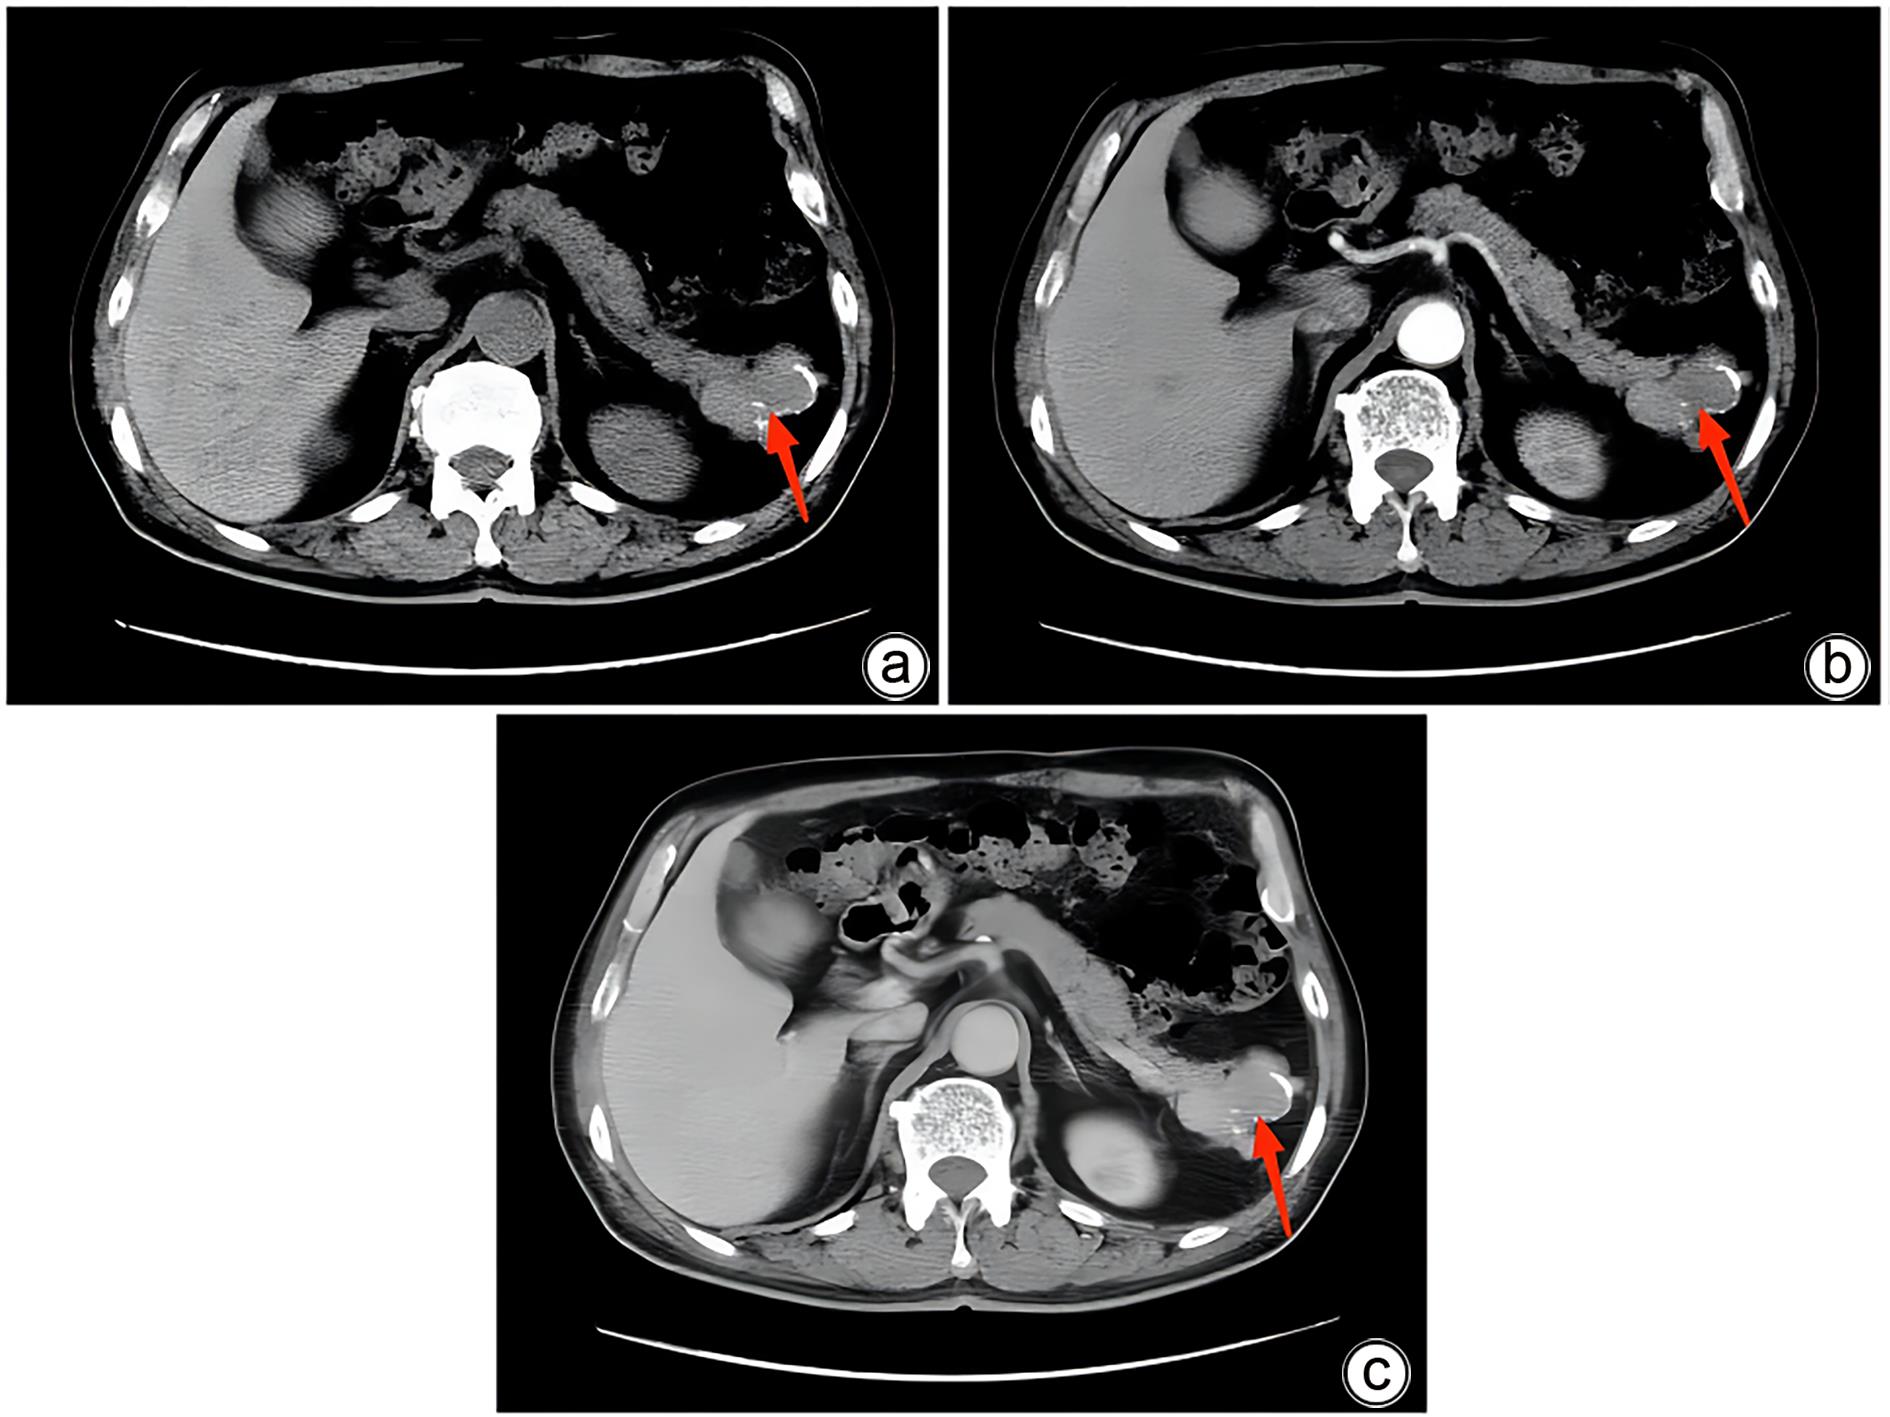

胰腺内副脾误诊2例报告

摘要(1364) HTML (331) PDF (1188KB)(158)

副脾是指正常脾脏以外存在的,与主脾结构相似,有一定功能的脾脏组织,其中完全被胰腺包裹的胰腺内副脾(IPAS)发生率仅为2%,因其临床症状不典型,影像学特征与胰腺神经内分泌肿瘤、胰腺实性假乳头状瘤以及其他胰腺占位性病变较为相似,临床上容易误诊。本文报道了2例分别被误诊为胰腺神经内分泌肿瘤和胰腺实性假乳头状瘤的IPAS患者,并分析误诊原因,总结诊疗经验,以期提升临床对IPAS明确鉴别诊断的认识。